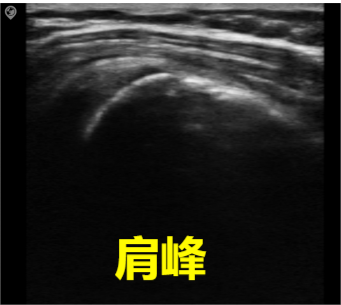

Common frequency range: 5.0MHz-16.0MHz,

Common scan width: 30-40mm,

Imaging depth: within 6cm from the skin.

Features: The probe surface is flat, with a large contact area, rectangular imaging field of view, high imaging resolution, and relatively low penetration depth; suitable for examination of superficial vessels, small organs, musculoskeletal structures, etc.